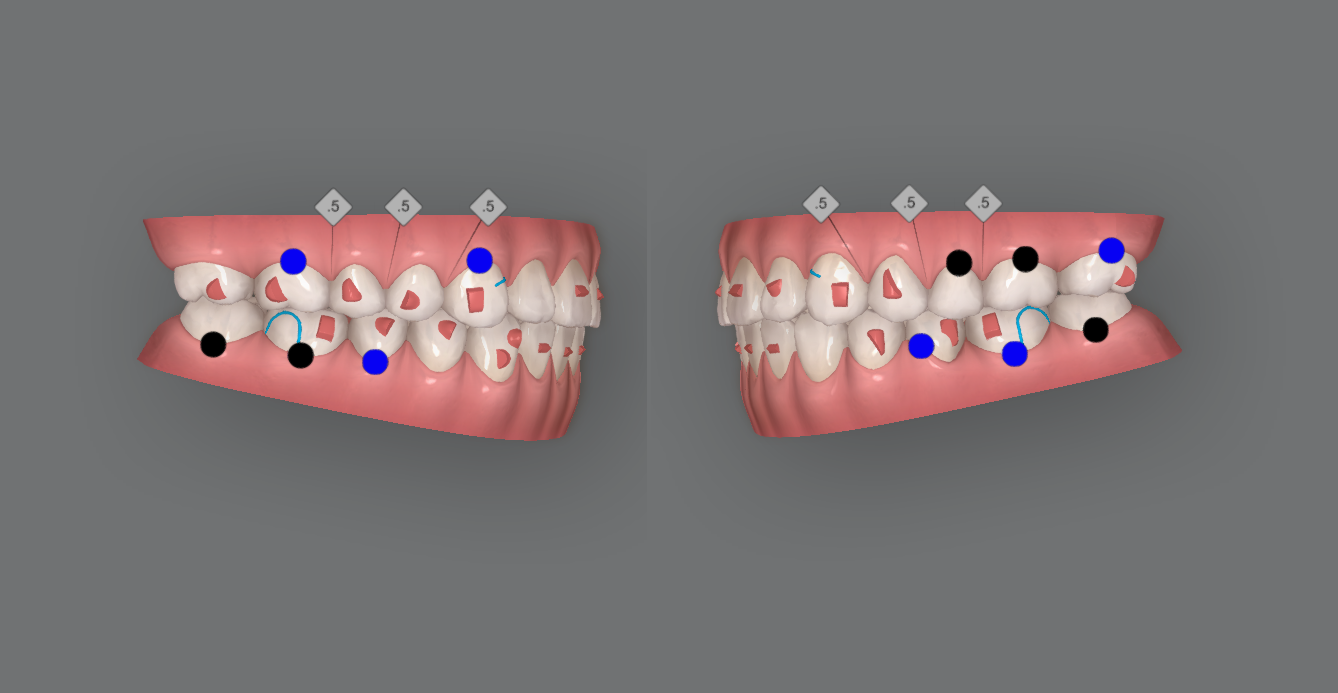

Kết quả đạt được

- Đạt tương quan khớp cắn loại I

- Hai cung hàm được sắp xếp và phối hợp

- Cải thiện hình dạng cung hàm

- Đạt được sự hài hòa giữa hai cung hàm

- Tương quan răng cối và răng nanh đã được điều chỉnh

- Đạt tương quan overjet và overbite bình thường

- Cắn hở vùng răng trước được điều trị bằng intrusion răng sau và extrusion răng trước